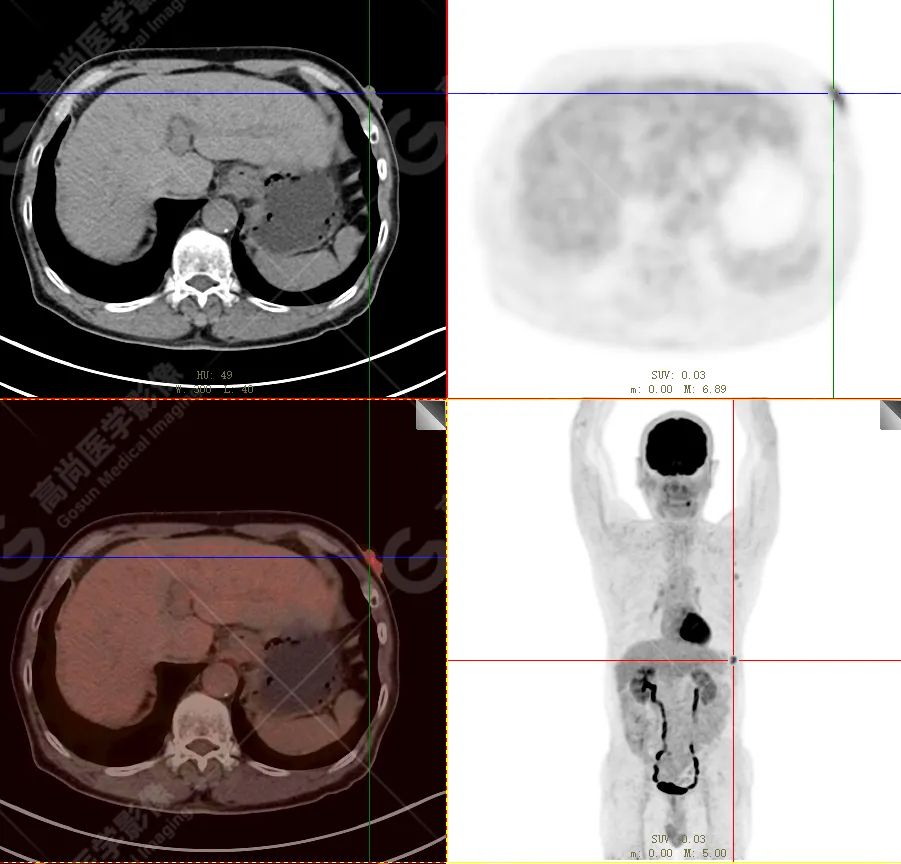

PET/CT 示:

左下胸壁(约左侧第 8 前肋水平)皮肤见一小片状放射性摄取轻度增高影,范围约 0.8 cm×2.2 cm×1.6 cm,SUV 最大值为 3.9,CT 于上述部位见异常软组织密度影,边界尚清,密度尚均匀,CT 值约 40.0 Hu,局部突出体表。

PET/CT 结论:

左下胸壁(约左侧第 8 前肋水平)皮肤小片状代谢轻度增高灶,结合病史,考虑为恶性肿瘤(黑色素瘤)。

病理结果:

符合黑色素瘤(结节型)。